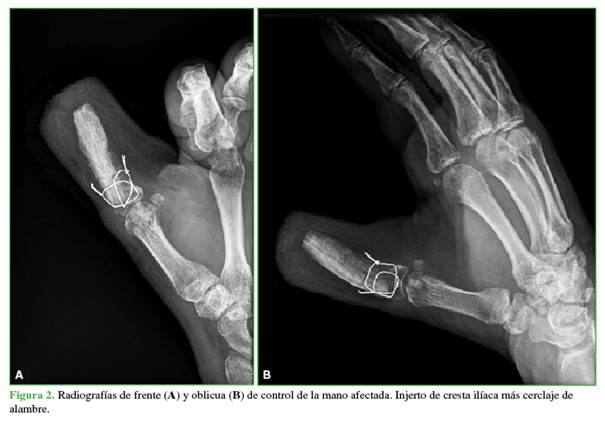

3)                  Fijación de la cresta ilíaca: se estabilizó el injerto con el remanente de base de falange proximal con cerclaje de alambre en los planos coronal y sagital de la articulación metacarpofalángica, suplementado con alambres de Kirschner temporales. Si hay remanentes tendinosos, se podría realizar una tenoplastia, que no fue necesaria en nuestro paciente (Figura 2).